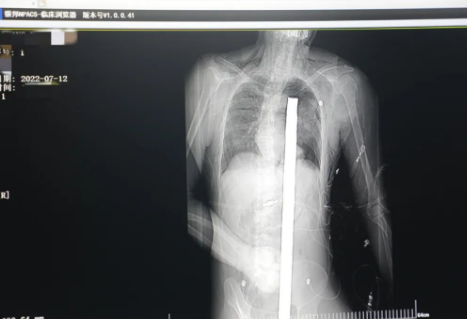

突發(fā)!太疼了,1.2米長(zhǎng)的螺紋鋼從男子會(huì)陰部垂直穿入胸腔......7月12日下午16時(shí)10分,西安一處工地的一名26歲工友,不慎從10多米的高空墜落,不幸的是工地上一根直徑3厘米的螺紋鋼從男子會(huì)陰部垂直穿入體內(nèi),工地上的工友們小心翼翼地將連著的鋼筋截?cái)?。情況危急,立即送往西安國(guó)際醫(yī)學(xué)中心醫(yī)院急救中心,此時(shí)正是下午17時(shí)00分。

時(shí)間就是生命!此時(shí),西安國(guó)際醫(yī)學(xué)中心醫(yī)院展開(kāi)了一場(chǎng)與生命賽跑的搶救,第一時(shí)間開(kāi)辟綠色通道,急診X光片及CT顯示:異物經(jīng)會(huì)陰部貫穿盆腔、腹腔到達(dá)左側(cè)胸腔主動(dòng)脈弓水平。醫(yī)院創(chuàng)傷中心立即啟動(dòng)應(yīng)急預(yù)案,劉延彤副院長(zhǎng)親臨指揮,下午17點(diǎn)48分,當(dāng)患者被送達(dá)手術(shù)室,胸外、心外、肝膽外科、胃腸外科,泌尿外科及麻醉科等多學(xué)科專家聯(lián)手對(duì)這名工友進(jìn)行“縱劈胸骨 前外側(cè)開(kāi)胸探查 氣管及主支氣管修補(bǔ) 肺修補(bǔ) 血胸清除 開(kāi)腹探查止血 腹膜后及盆腔探查......”手術(shù)。

情況緊急!術(shù)中探查后發(fā)現(xiàn),長(zhǎng)120cm直徑3cm的螺紋鋼經(jīng)患者右側(cè)會(huì)陰部穿入,傷及直腸,途徑膀胱后方,左側(cè)髂總動(dòng)靜脈之間傷及左腎后,經(jīng)胰腺后方在肝脾之間穿破膈肌,在下肺靜脈前方穿入左肺穿破氣管及左右主支氣管膜部,止于主動(dòng)脈弓下水平,穿入體內(nèi)的部分達(dá)到75cm。